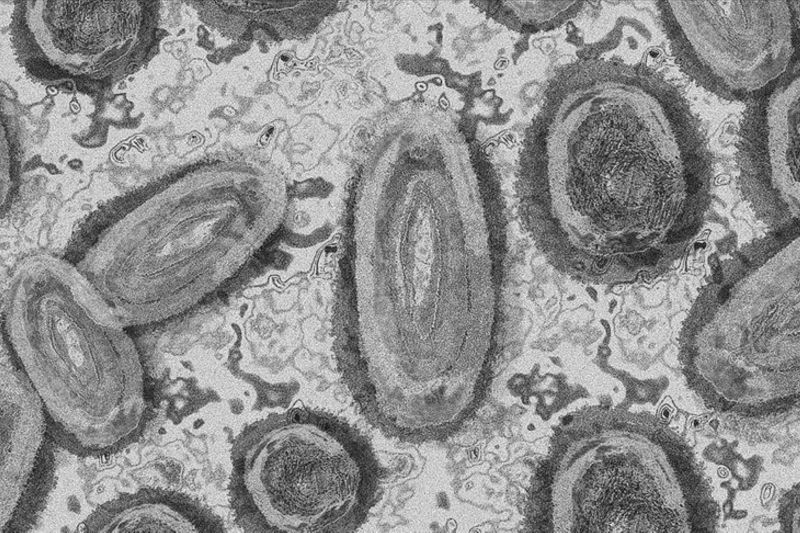

ilustrasi virus cacar monyet di Swedia/ANTARA/Anadolu/PY

London (ANTARA) - Swedia pada Kamis melaporkan kasus pertama varian cacar monyet (mpox) yang lebih menular di luar Afrika, menurut laporan media lokal.